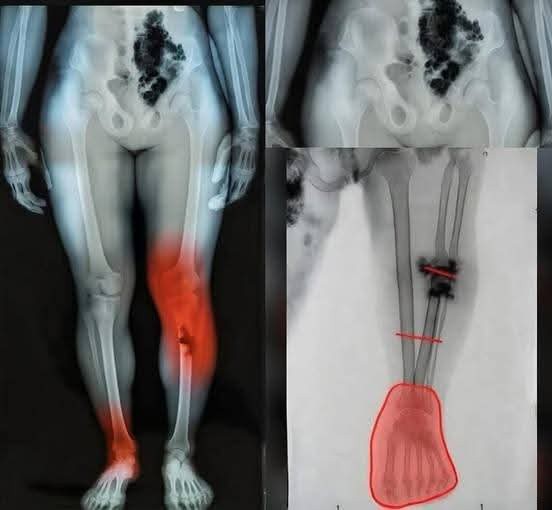

El sorprendente caso de Tomm Tennent: el bebé que desconcertó a la medicina y desafió todos los pronósticos